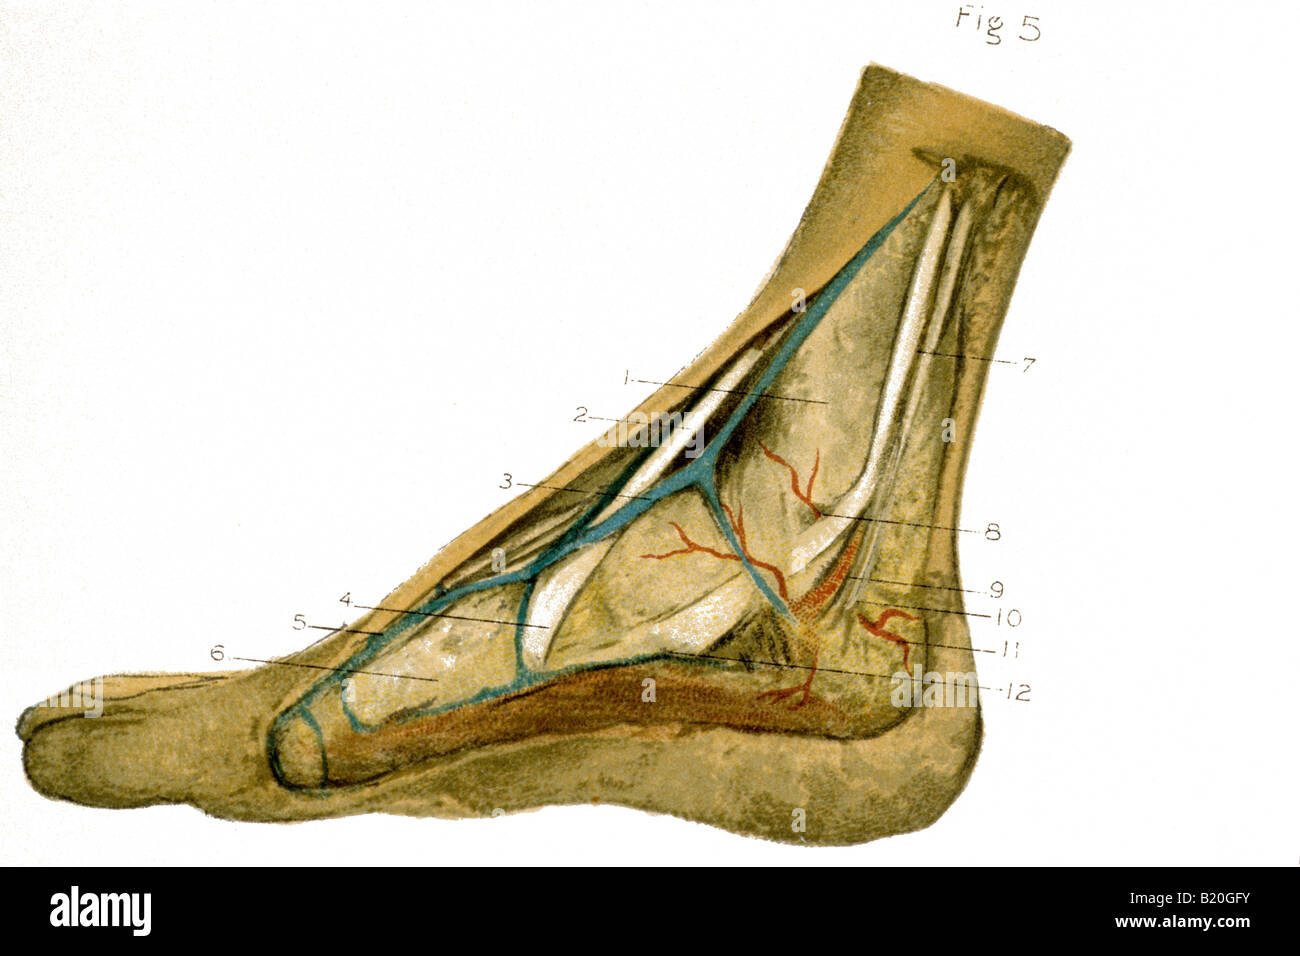

RFPR8GRD–19ème siècle illustration de la jambe gauche de l'avant après avoir enlevé la peau et le fascia. Publié dans Bilder-Atlas Conversations-Le Systematischer zum